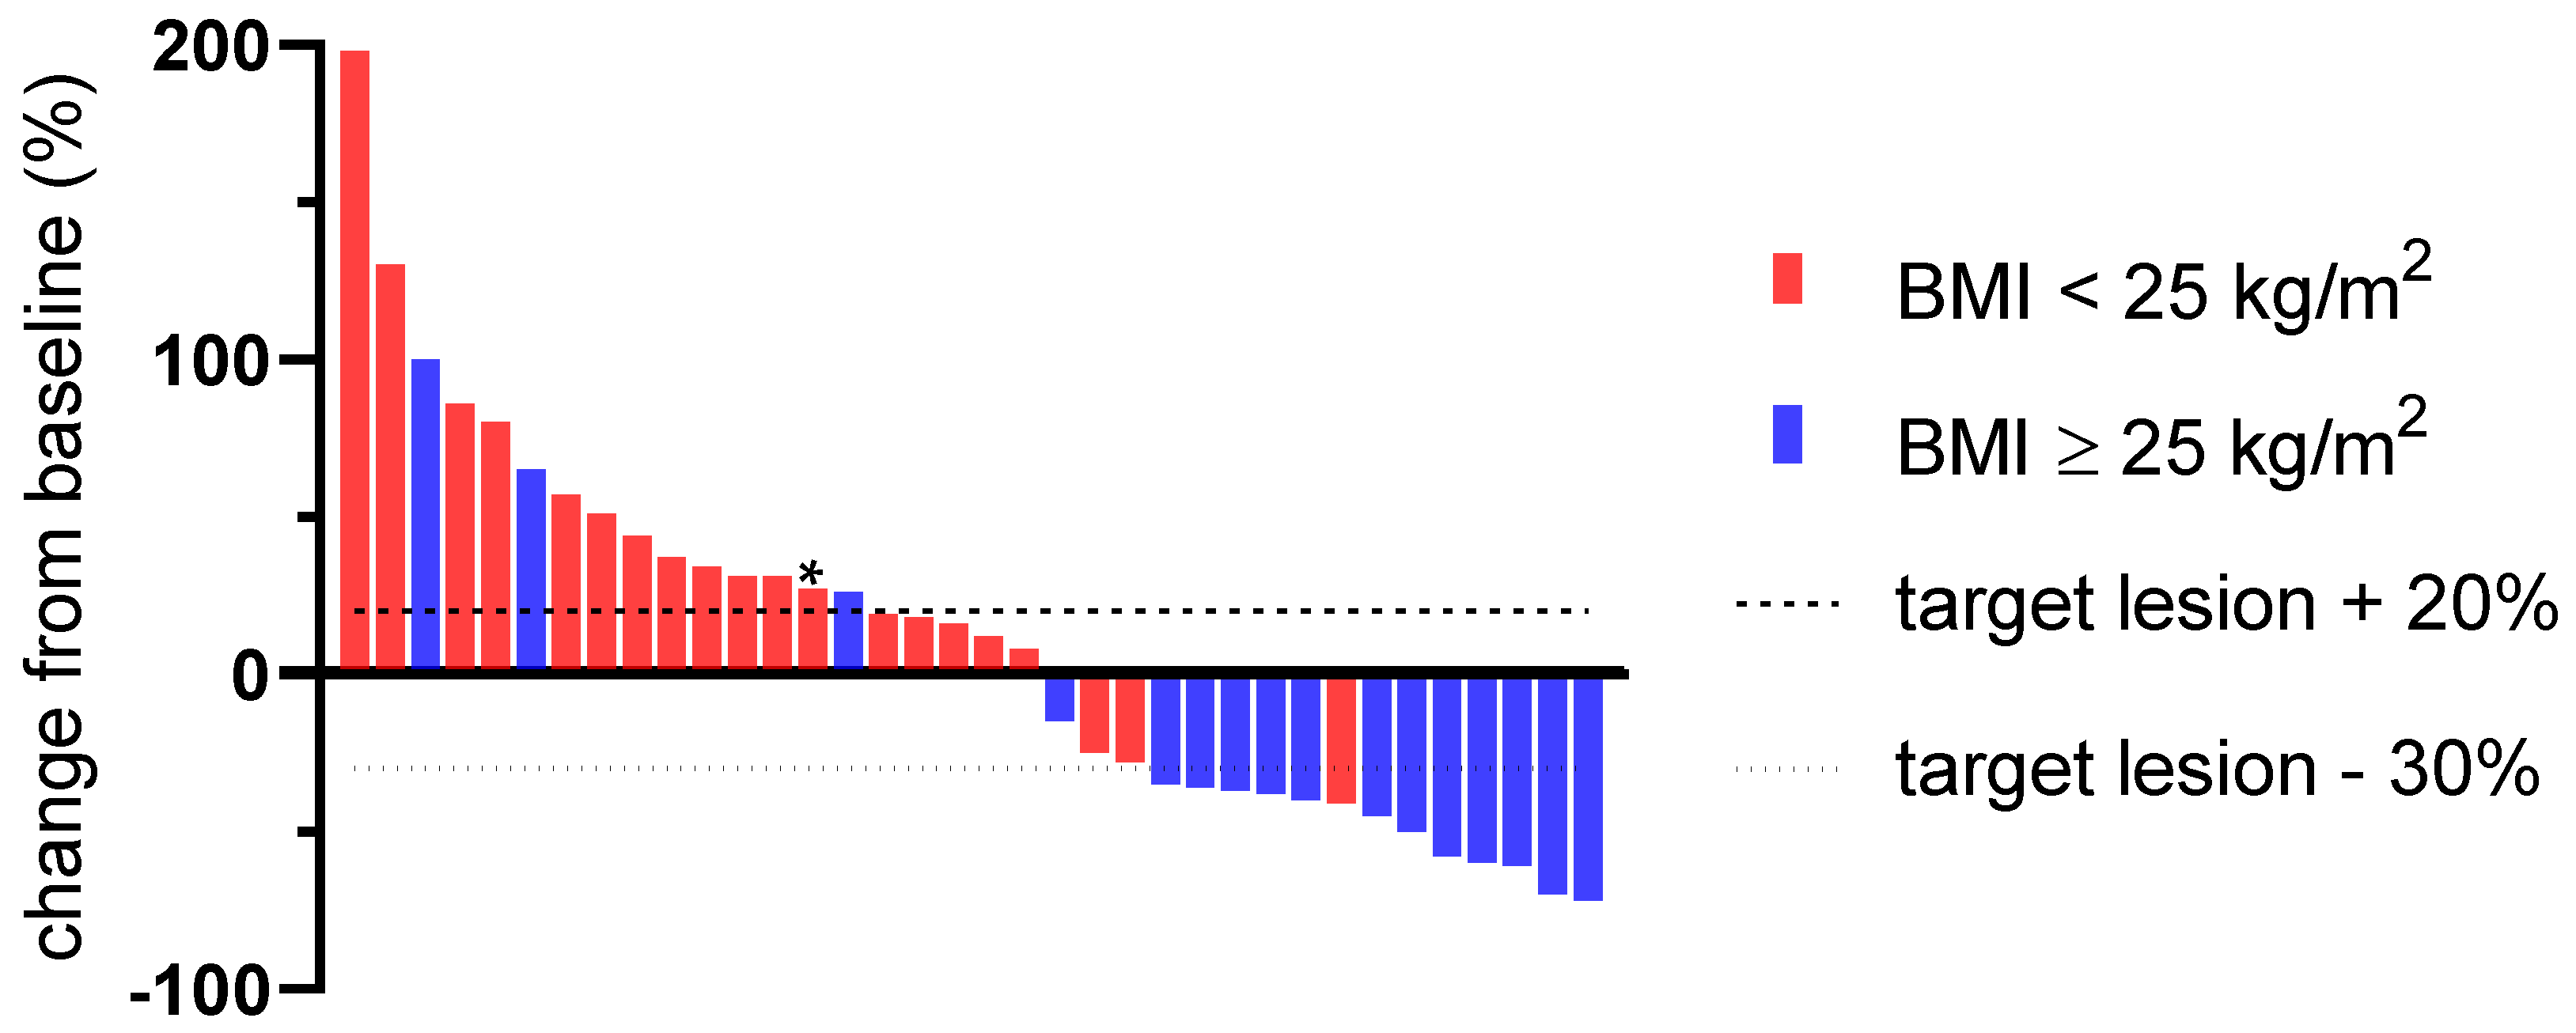

3.2. Predictive Value of a Pretherapeutic BMI for CPI Therapy

| overall response rate (ORR) | 36.1% (13/36) | 5.0% (1/20) | 75.0% (12/16) | <0.001 * |

| disease control rate (DCR) | 58.3% (21/36) | 40.0% (8/20) | 81.3% (13/16) | 0.023 * |